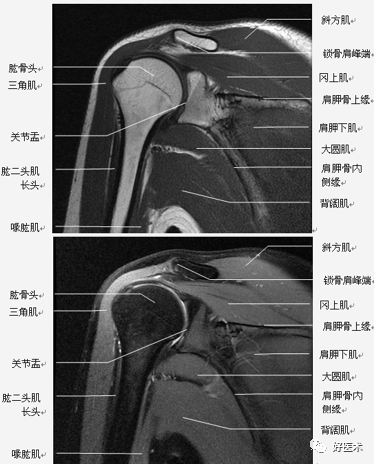

(2)扫描方位

-

横轴位:取三维立体定位像的冠状像,扫描层面与关节盂垂直,扫描范围从肩峰至肱骨颈下。

斜冠状位:取横断位作定位像,扫描层面与冈上肌腱平行,扫描范围为锁骨外端至肩峰。

斜矢状位:取横断位作定位像,扫描层面与关节盂平行,扫描范围包括肱骨头和整个关节盂。

轴位:评估Bankart lesions 和盂唇损伤、评估肩胛下肌肌腱。

斜冠状、斜矢状:显示肩袖及冈上肌走行、显示喙肩弓。

斜冠状、轴位:评估盂唇撕裂、肱二头肌长头腱与上盂唇的连接。

轴位:显示肩胛下肌腱撕裂、盂唇撕裂

冠状位:显示肩袖撕裂、盂唇撕裂

矢状位:显示肩袖撕裂、盂唇撕裂